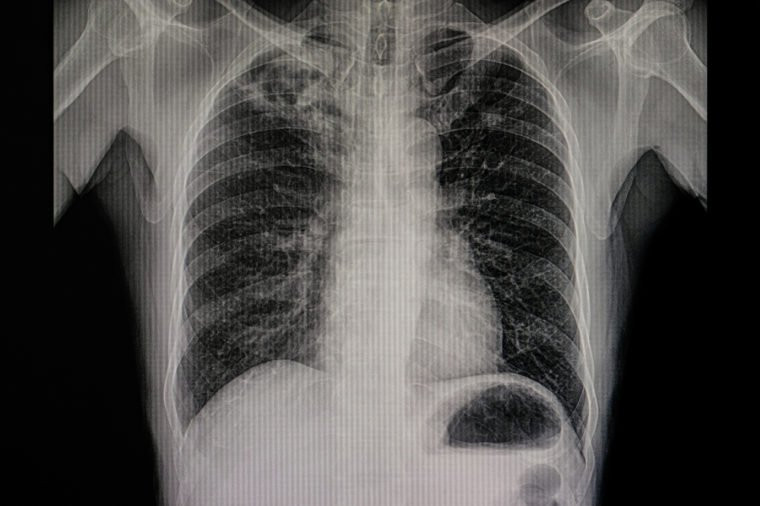

Nhiễm trùng đường hô hấp dưới: Theo số liệu của WHO, số người tử vong vì mắc các bệnh nhiễm trùng hô hấp dưới là 3,1 triệu người hay 5.5% các ca tử vong trên toàn cầu. Nhóm các bệnh này bao gồm viêm phổi, viêm phế quản và cúm.